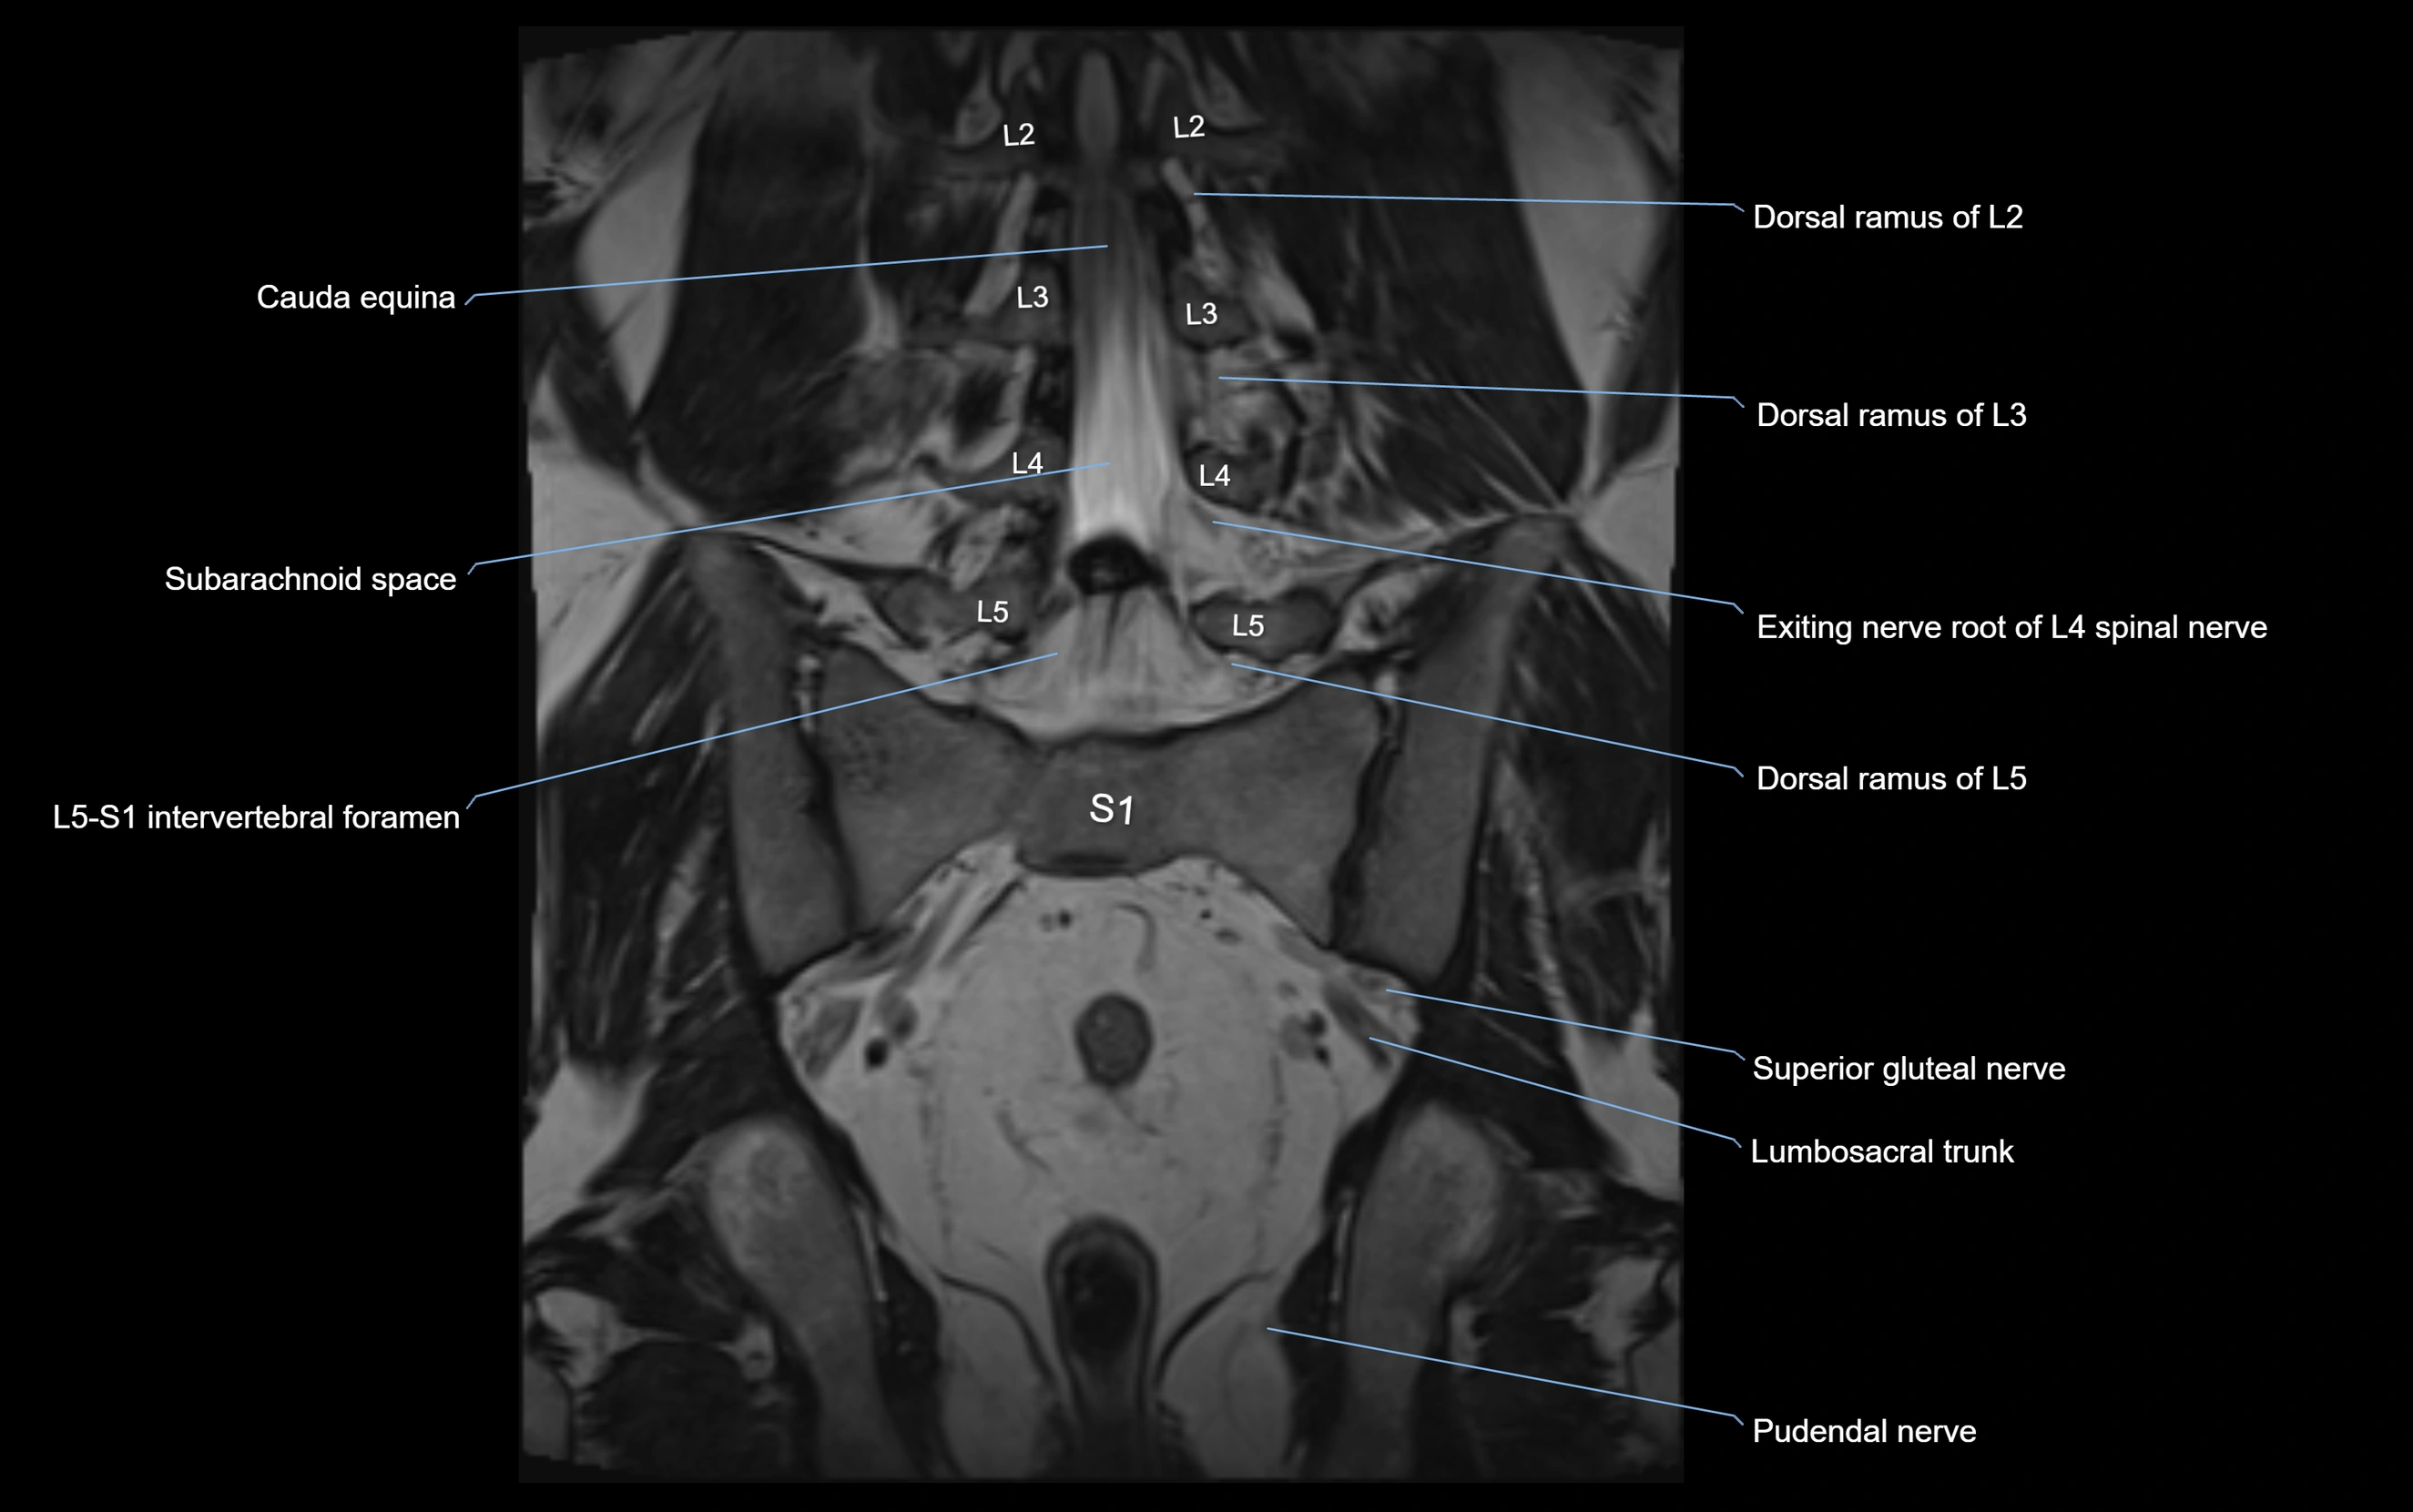

MRI Appearance

T1-weighted images:

• Nerve appears as a very thin low-to-intermediate signal intensity structure

• Surrounded by bright fat, aiding visualization

T2-weighted images:

• Nerve shows intermediate to mildly hyperintense signal compared to muscle

• Pathological involvement appears brighter

STIR (Short Tau Inversion Recovery):

• Normal nerve appears dark

• Inflamed or entrapped nerve appears bright hyperintense

T1 Fat-Sat Post-Contrast:

• Normal nerve enhances minimally

• Pathologic nerve (neuritis, entrapment, tumor infiltration) shows focal or diffuse enhancement

3D T2 SPACE / CISS:

• Nerve appears intermediate to mildly hyperintense compared to muscle

• Surrounded by bright fat or CSF, improving visualization

• Best sequence for mapping small pelvic nerves such as the anococcygeal